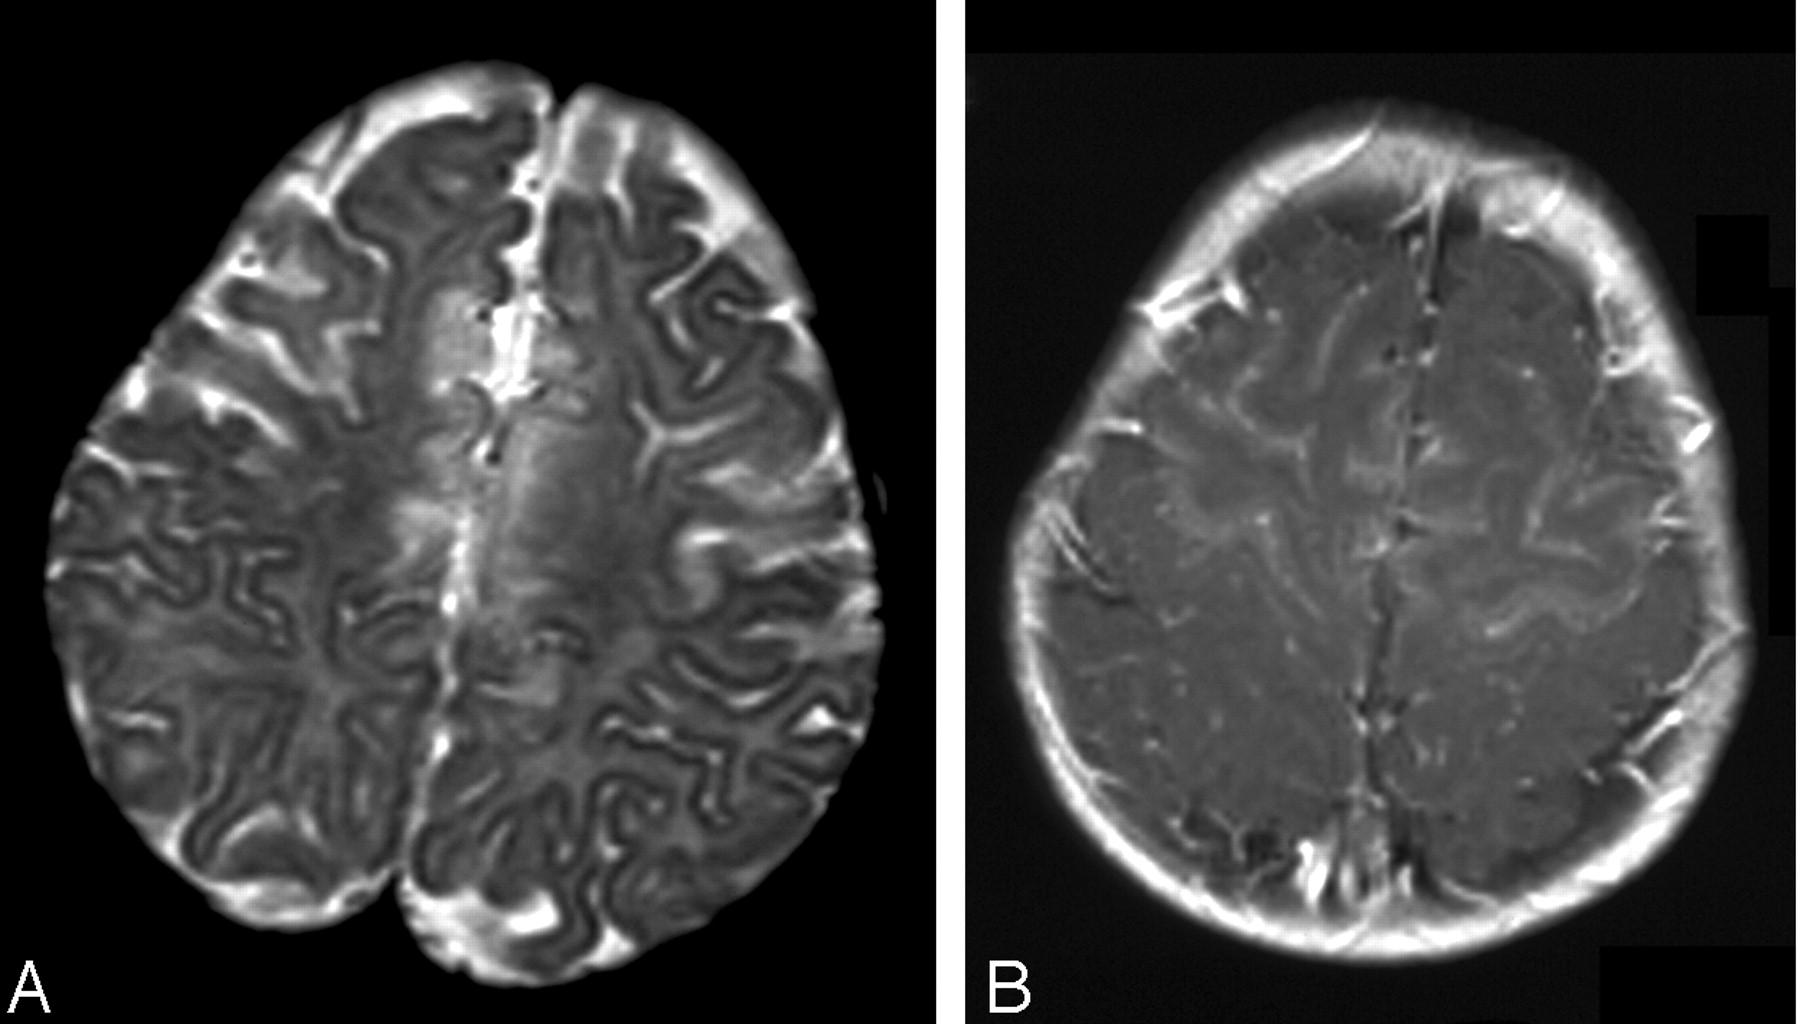

Patient 4. Axial images at presentation.

A, T2-weighted image.

B, T1-weighted contrast-enhanced image shows extensive frontal injury. Note enhancement of both cortex and white matter.